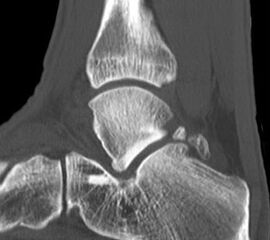

Abbildung Nr. 14-16

Reseziertes Os trigonum sowie prä- und postoperatives seitliches Röntgenbild nach arthroskopischer Entfernung eines Os trigonum.